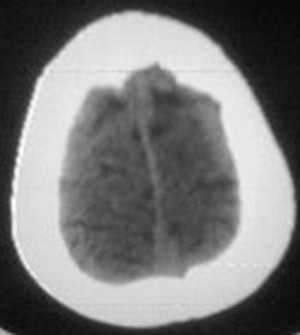

额骨垂直板上中部见椭圆形低密度区,边界清楚,硬化,膨胀,前方皮质断裂。

病变的起源应该是板障。

考虑:皮样囊肿可能性大。